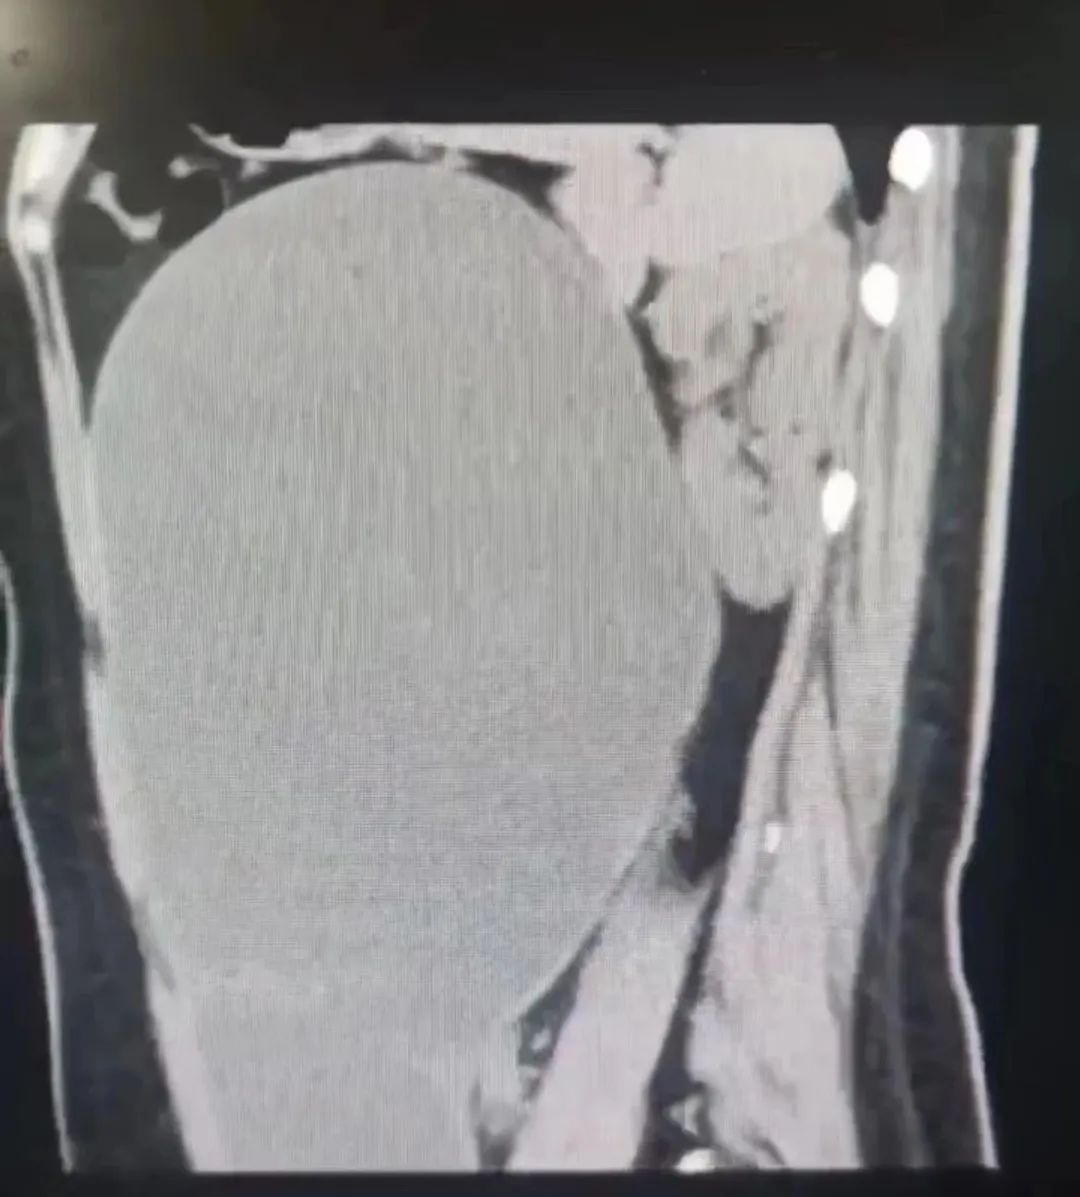

「从影像上看,巨大的包块占满了腹腔、盆腔的大部分空间,并推挤其他器官,造成了肠管、胰腺、左肾的移位,考虑是子宫附件的囊肿,浆液性囊腺瘤,良性病变的可能性大。」

辛晓燕教授门诊看过后解释,包块里面充满了液体,所以从外观来看,小美的肚子是一整片均匀鼓出,按压时也并不坚硬,这才造成了她长胖的错觉。

术中,腹腔镜从肚脐处打孔进入小美体内,镜下看到「粉白色」的「大水球」紧贴着腹壁,从左侧卵巢长出,上达腹腔最顶端,下至盆腔最底端,直径大小超过 20 公分,堪比「足月妊娠」。

手术共抽出了约 5000 毫升、10 斤左右的液体,比一般足月的新生儿都重。